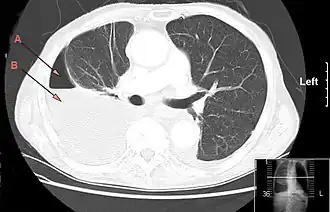

Examens radiologiques

La radiographie thoracique de face et de profil est faite avant la ponction[14],[20]. Elle peut retrouver soit un épanchement pleural libre, soit un épanchement enkysté.

L'échographie pleurale simple localise une collection enkystée, un cloisonnement éventuel et un épaississement pleural. Elle guide la ponction pleurale.

En général, le scanner thoracique se fait en seconde intention, à la recherche d'une cause et de lésions associées (en dehors de l'infection)[20]. Il permet également d'explorer la morphologie de l'épanchement, et notamment de rechercher la présence de cloisonnements ou d'enkystement avant drainage pleural ou chirurgie. Cela permet de guider le geste et d'éviter une plaie pulmonaire lors de sa réalisation.